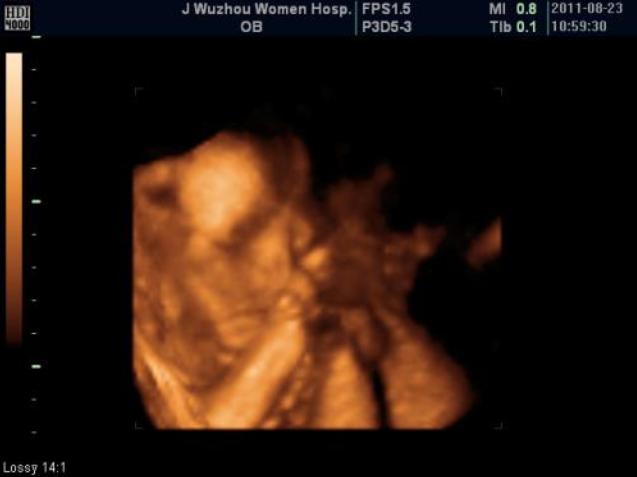

四维超声则是在三维彩超的基础上增加了时间维度,通过三维容积探头连续采集图像,同时进行同步立体图像的数据处理,获得实时动态的胎儿的立体结构图像,能实时捕捉到胎儿的运动,可有效筛查胎儿畸形。

当然,很多医院也为了迎合孕妈妈的心理,大家都想知道胎儿的长相,留下一张胎儿的纪念照片,所以好多医院所宣传的四维彩超,其实只是将胎儿系统彩超检查中的一个三维图像打印出来而已,也就变成了大家所说的胎儿四维彩超了。

目前,多数医院都会在孕期安排2次进行系统畸形筛查的四维彩超,第一次在22周左右比较好,第二次在32周左右比较好。